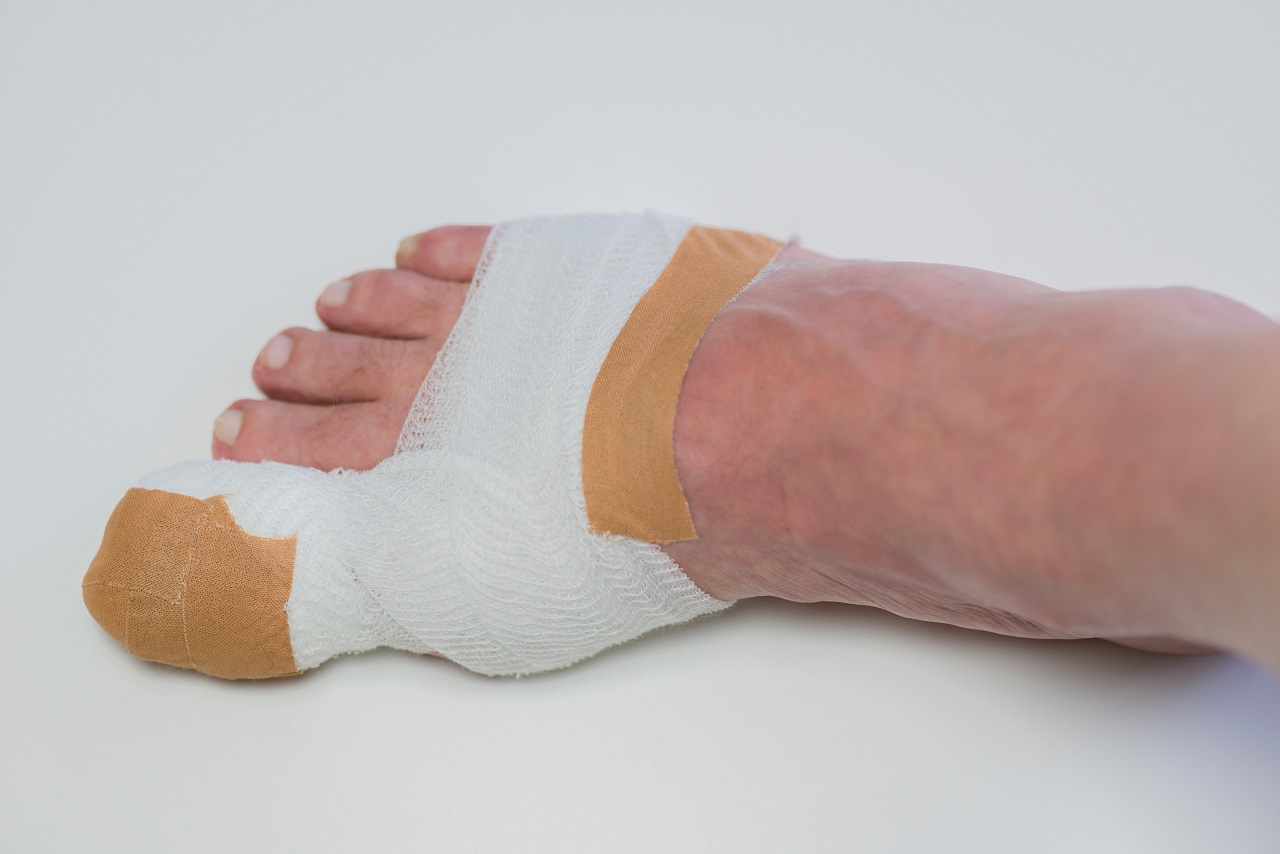

- Наложите мягкую компрессионную повязку (не туго).

- При сильной боли допустим прием НПВС (например, ибупрофен) при отсутствии противопоказаний.

- Иммобилизация. При выраженной боли или риске осложнений палец фиксируют мягкой повязкой или лангетой. Это уменьшает нагрузку и позволяет тканям восстановиться.

- Хирургическая помощь. При обширной гематоме или сильном повреждении ногтя врач выполняет дренирование — прокалывает пластину и выпускает кровь. В результате давление снижается, боль уходит. Если ноготь частично оторван, его фиксируют; при полном отслоении — удаляют, обрабатывают ложе, накладывают асептическую повязку. В тяжелых случаях ногтевую пластину удаляют полностью.